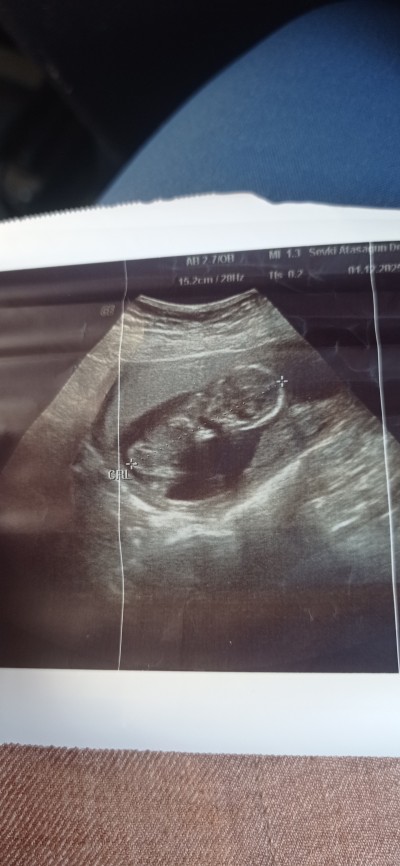

Cinsiyet tahmini yaparmisiniz doktor kız gibi duruyor dedi 1 ay sonra söylerim dedi.

Gebelik haftası 13.3

Çok bulanık. Gerçi ben de anlamam da 😄 Erkek dese değişme oranı düşük oluyor diyorlar. Kız dediyse belli olmaz kendini ikisine de hazırla:)

Aynı bende 13 haftalık hamileyim kız gibi duruyor dedi 1 ay sonra gel bakalım dedi net belli değil değişebilir mi onu da bilmiyorum açıkçası